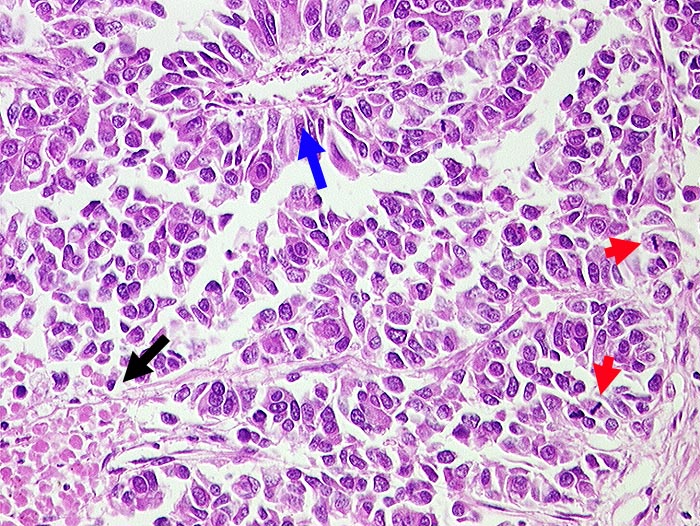

Grosszelliges neuroendokrines Karzinom

Mittelgrosse Tumorzellen mit reichlich Zytoplasma und zahlreichen Mitosen. Herdförmige Nekrosen. Pseudorosettenbildung um Gefäss.

Zentrales Bronchuskarzinom. Synaptophysin und NSE positiv.